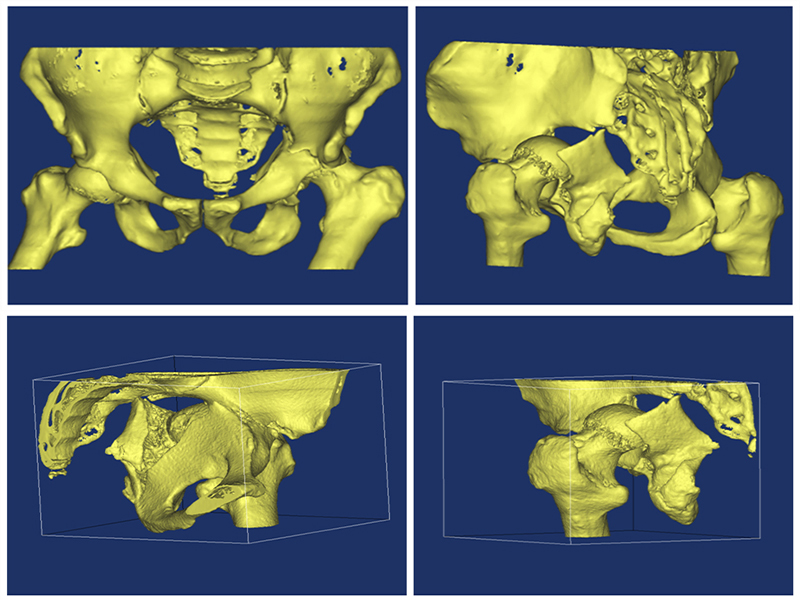

MIMICS CT 360º K L

(1).jpg)